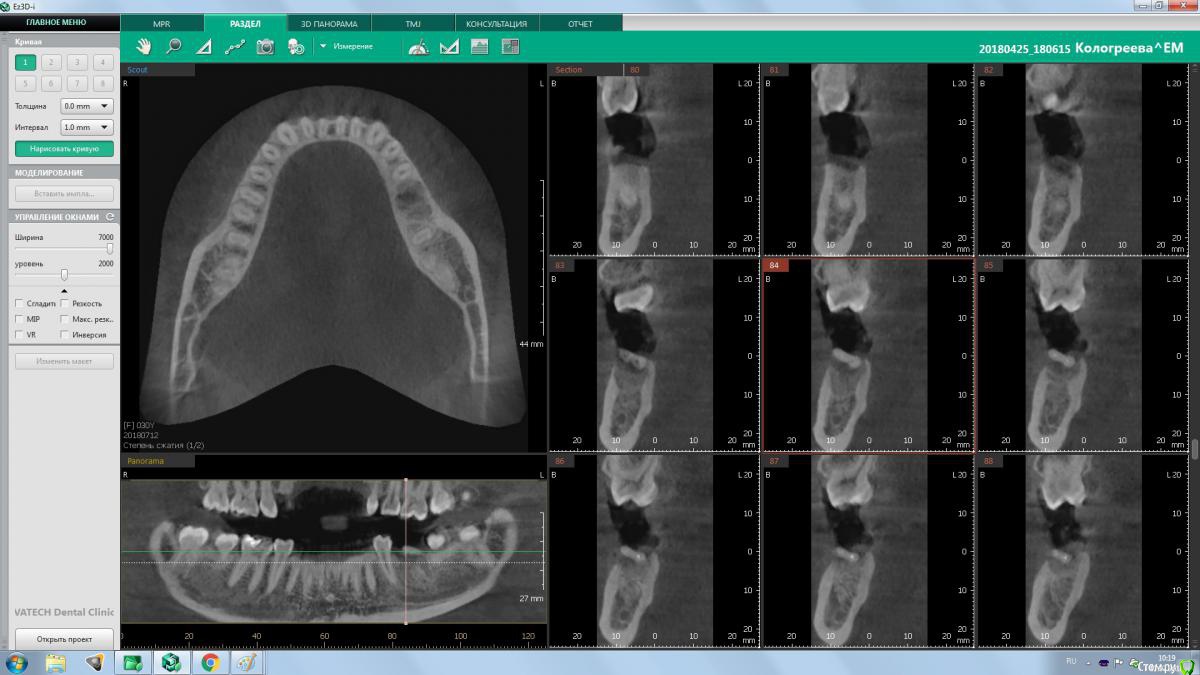

колесников Опубликовано 10 августа, 2018 Поделиться Опубликовано 10 августа, 2018 (изменено) Ещё один случай. Время ожидания 3-4мес. Одну ногу как говорится побрил,а другую оставил обрастать. Пробка только на 36ом. В лунках графт. У 37 более выражен лизис стенок альвеолы, и это всего за 3 мес. У 36ого, как водится, анатомический контур десны Изменено 10 августа, 2018 пользователем колесников 5 Ссылка на комментарий